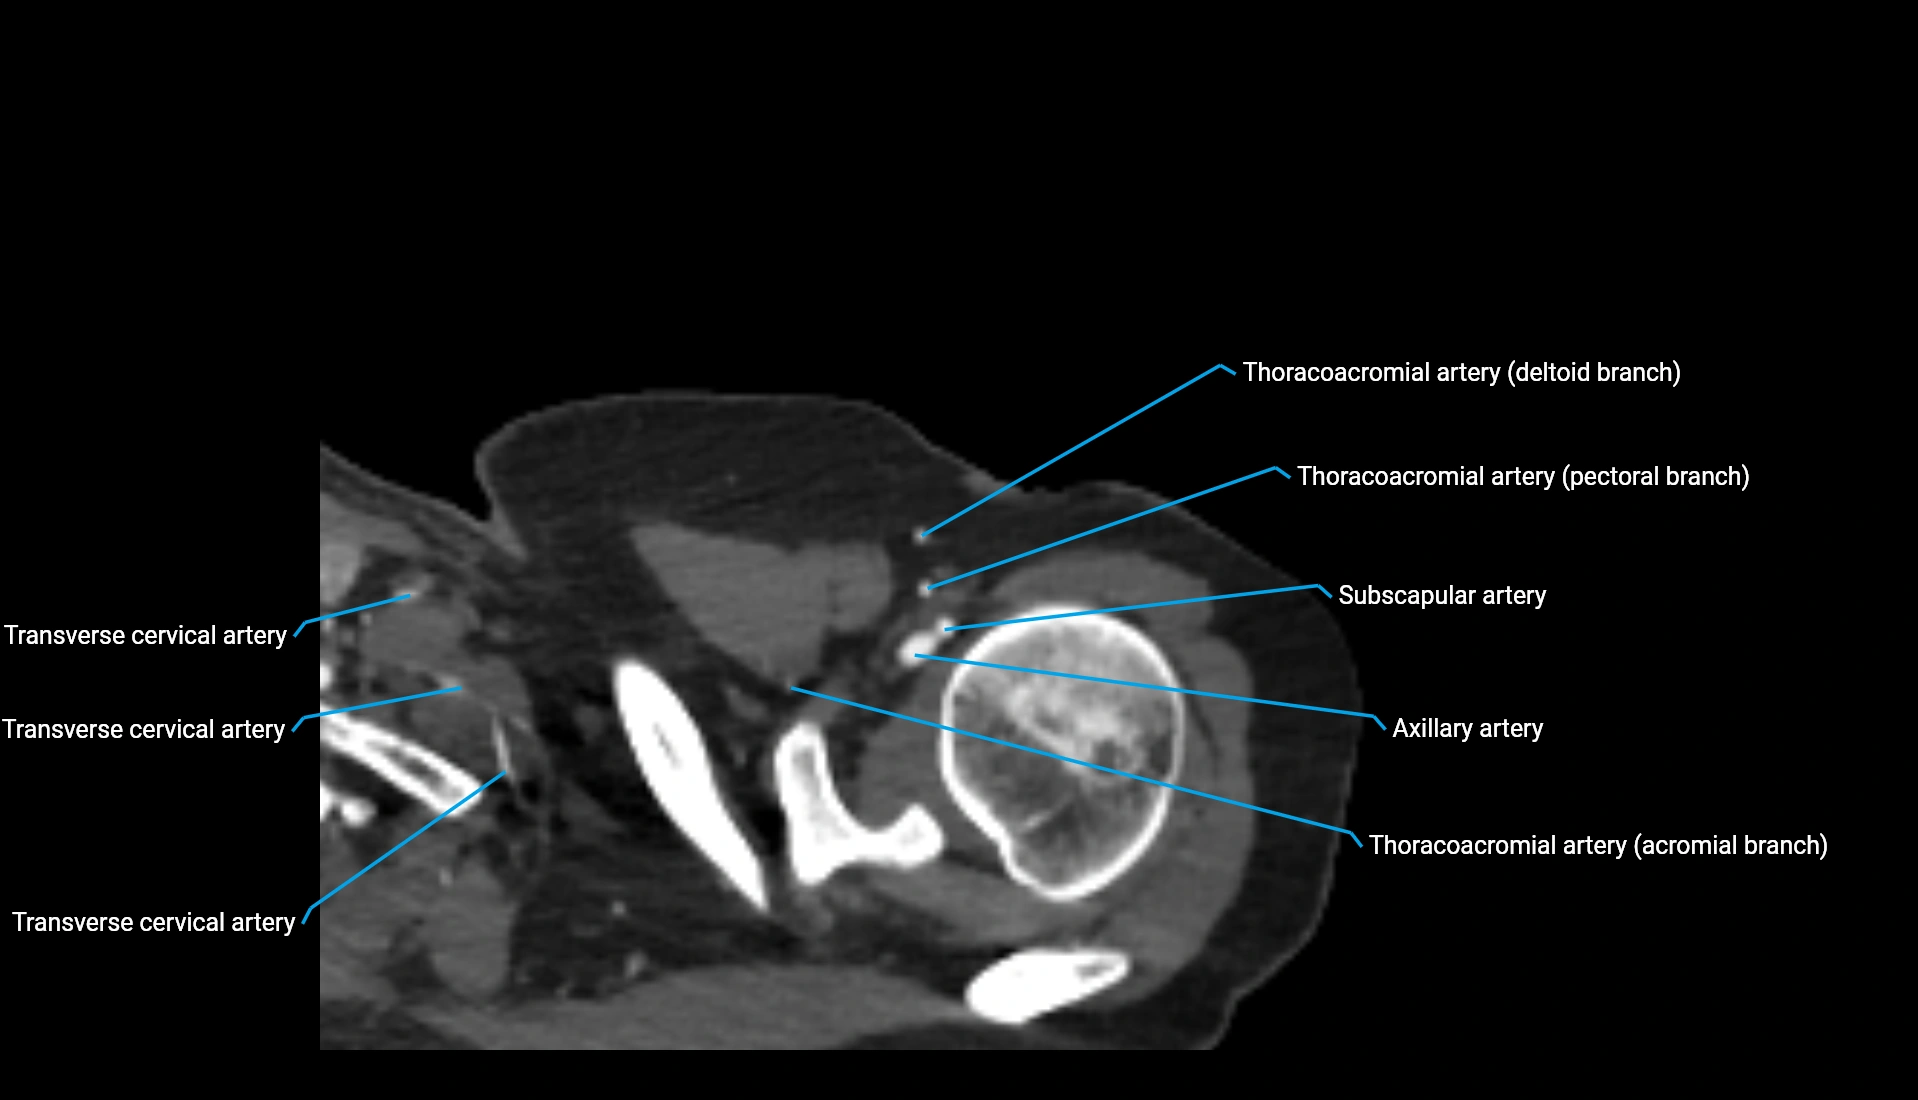

CT Appearance

Non-Contrast CT:

• Cortex: High-density, sharply defined

• Subchondral bone: Dense cancellous matrix

• Articular surface: Smooth concave contour articulating with the capitellum

• Excellent for evaluating bone integrity, alignment, and subtle fractures